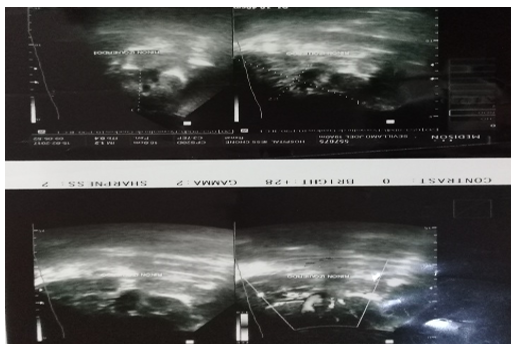

El informe de la ecografía de abdomen reflejó hígado de tamaño normal, disminución de la ecogenicidad y ecoestructura granular fina en ambos riñones, prominencia de las paredes de los vasos portales, compresión del seno renal con mala diferenciación seno parénquima, bazo que no se visualiza y páncreas de características normales. Así, la correlación de hallazgos clínicos y ecográficos confirma hepatopatía e insuficiencia renal bilateral y la necesidad de corroborar el posible padecimiento de Sicklemia (figura 3).

Figura 3.Ecografía de abdomen

Fuente: historia clínica del paciente